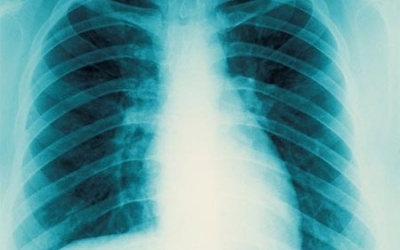

Ngày 12/3, tại Cà Mau, Viện nghiên cứu Y khoa Woolcock thuộc Trường đại học Sydney (Australia) phối hợp Chương trình chống lao Quốc gia thuộc Bộ Y tế tổ chức hội thảo khởi động dự án...